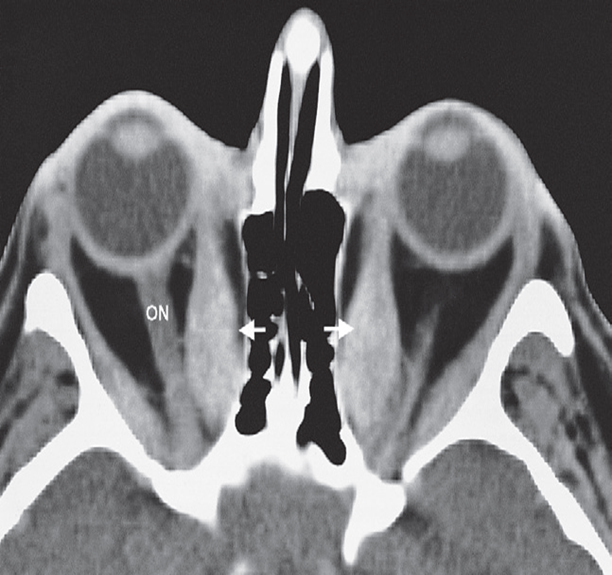

Thyroid eye disease. CT scan through the orbits

showing enlargement of the extraocular muscles, particularly the medial rectus (arrows). ON; optic nerve.